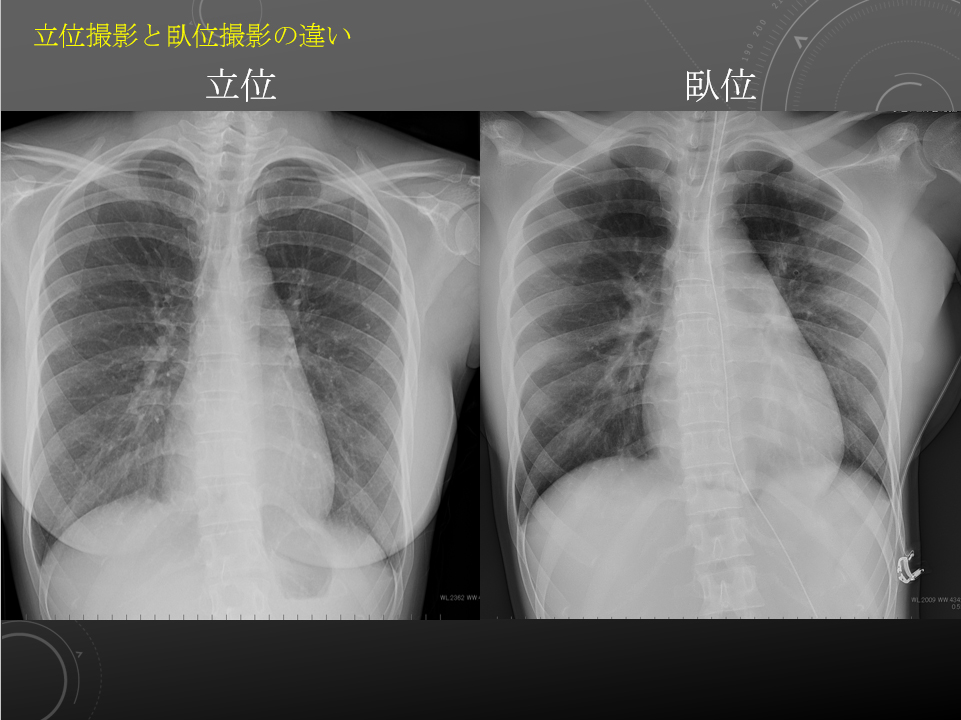

臥位と立位

臥位と立位